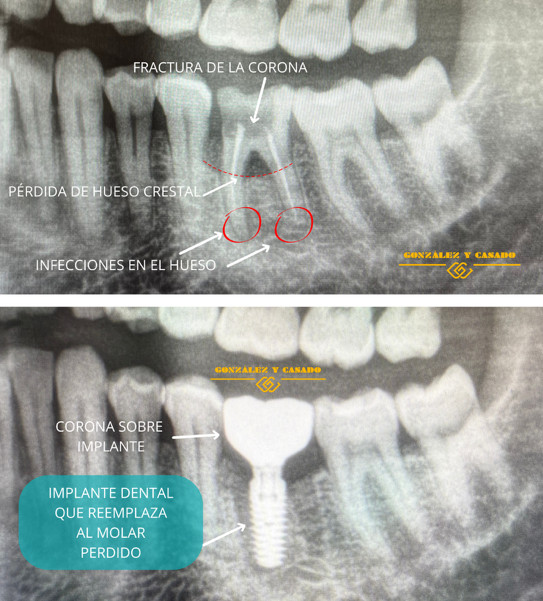

Un implante dental es un dispositivo de titanio con forma de tornillo que se coloca en el hueso maxilar o mandibular para sustituir la raíz de un diente perdido.

Tras su colocación, requiere un tiempo de cicatrización en el interior del hueso, para unirse con él llamado osteointegración). Este tiempo tiene lugar entre las 8 y 16 semanas post-cirugía. El paso final es la colocación de una corona o prótesis encima que imita la corona del diente o muela natural para recuperar la función y estética del diente.